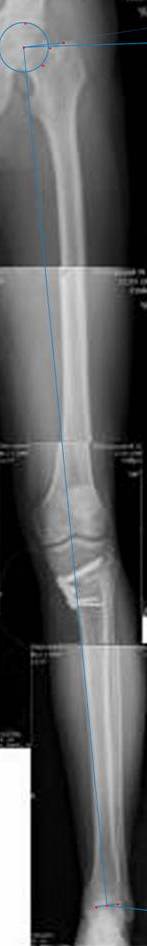

картинки оперированного пациента 40 лет, травма в 2006 году.

оперирован 06.11.2009г - корригирующая остеотомия большеберцовой кости.

Я картинку собрал с некоторыми погрешностями, если провести отвес от центра вращения головки бедра до середины голени (на пациенте),то имеется небольшой вальгус (гиперкоррекция)конечно она (гиперкоррекция) не достигает 10 гр, но 5 гр она достигает.

К сожалению, не очень удачный пример. Если верить Р-граммам, имеет место быть дисплазия мыщелков бедренной кости с наклоном суставной линии. Это уже создает сложности получения хороших отдаленных результатов. Кроме того, по классике, необходима гиперкоррекция с созданием вальгуса 7-10 градусов для максимальной разгрузки медиального отдела КС. Если верить укладке, то линия сустава имеет четкий варусный наклон, поэтому результат операции м.б. кратковременным. В этих случаях показана двойная остеотомия бедра и тибии.

Alexander Artemiev 10 Ноябрь 2009, 15:54

Впечатление искажает неправильная укладка.

Если сделать правильно, то видно, что бедренная кость в порядке, а цель остеотомии (низкой, кстати), не достигнута вовсе.

Сохраняется варус. Для того, чтобы создать вальгусную гиперкоррекцию, не моделируя при этом откровенный Х голени, можно сделать медиализирующую остеотомию.